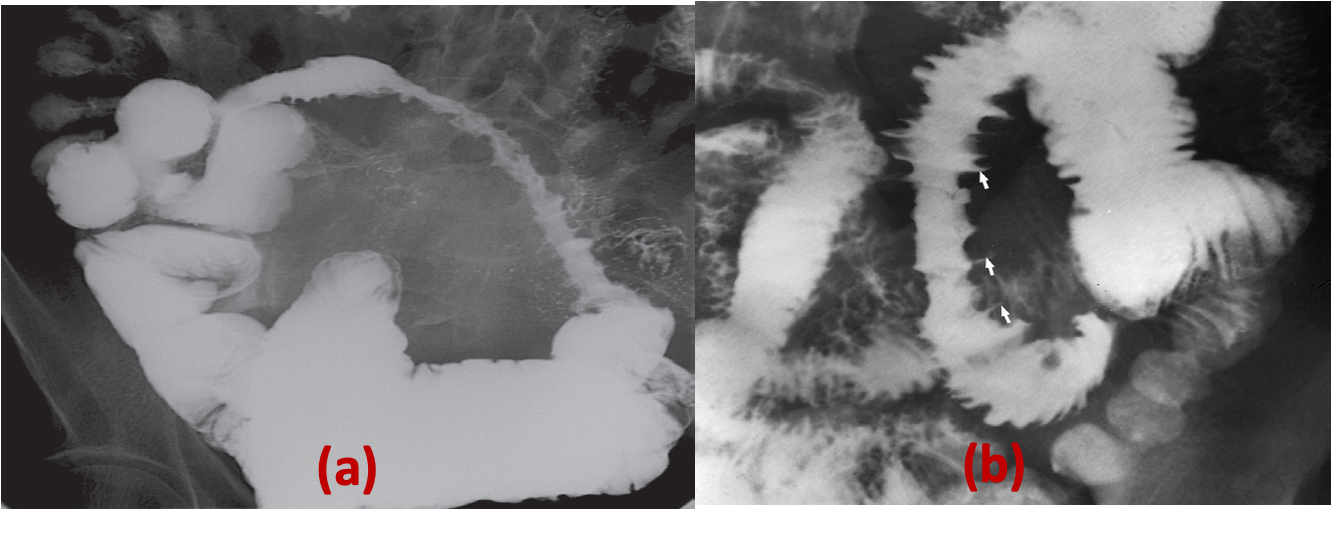

A) Narrowing. There is a long stricture in the ileum due to Crohn’s disease. There is also separation of the abnormal segment from other loops of the bowel.

B) Ulceration. Abnormal loops of bowel in Crohn’s disease showing the ulcers as outward projections.